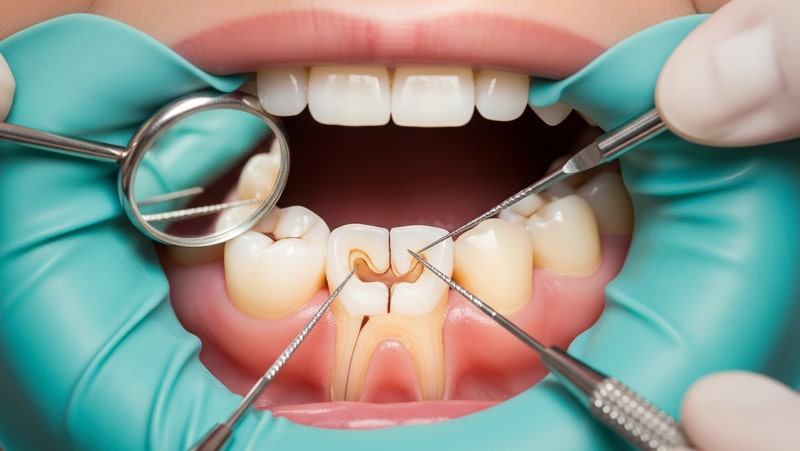

درمان ریشه دندان (Root Canal Therapy) زمانی انجام می شود که پوسیدگی عمیق یا آسیب، به بخش داخلی دندان یعنی پالپ (شامل عصب و عروق خونی) نفوذ کرده و موجب عفونت، درد یا التهاب شده باشد.

در این فرآیند، دندانپزشک ابتدا عصب و بافت پالپ آسیب‌دیده یا عفونی را از فضای داخلی دندان خارج می‌کند، سپس کانال‌های ریشه را به‌طور کامل تمیز، ضدعفونی می‌نماید. در مرحله بعد، این فضا با مواد مخصوص پر و آب‌بندی می‌شود تا از نفوذ مجدد باکتری ها جلوگیری گردد.

اعصاب و عروق اصلی دندان در یک بافت نرم قرار گرفته است که محل آن کانال های ریشه دندان می باشد. به این بافت نرم در اصطلاح پالپ می گویند و زمانی که دچار مشکلات معمول از جمله عفونت شود، شما نیاز دارید به درمان آن اقدام کنید. در چنین زمانهایی است که پیشنهاد دکتر به شما کمک گرفتن از روش درمان ریشه دندان می باشد.

می شود گفت زمانی که دندان فردی درگیر عفونت همراه با پوسیدگی می شود، تنها راه کمک درمان ریشه آن است. این نوع درمان به این طریق انجام می شود که ابتدا دندانپزشک اقدام به خارج کردن بافت خراب از ریشه دندان می کند. سپس باید کانال های ریشه دندان تمیز شوند و حفره های بوجود آمده توسط مواد ویژه پر گردند.

معمولا عفونت ایجاد شده در پالپ دندان ناشی از مواردی چون آسیب دیدگی، ترک و شکستگی و پوسیدگی های عمیق می باشد. از نشانه های این عفونت ها می توان به حساسیت دندان به دمای مایعات، خرابی قابل مشاهده دندان، تورم در ناحیه فک و لثه، درد و … اشاره کرد که با مشاهده آنها باید برای درمان ریشه دندان اقدام نمایید.